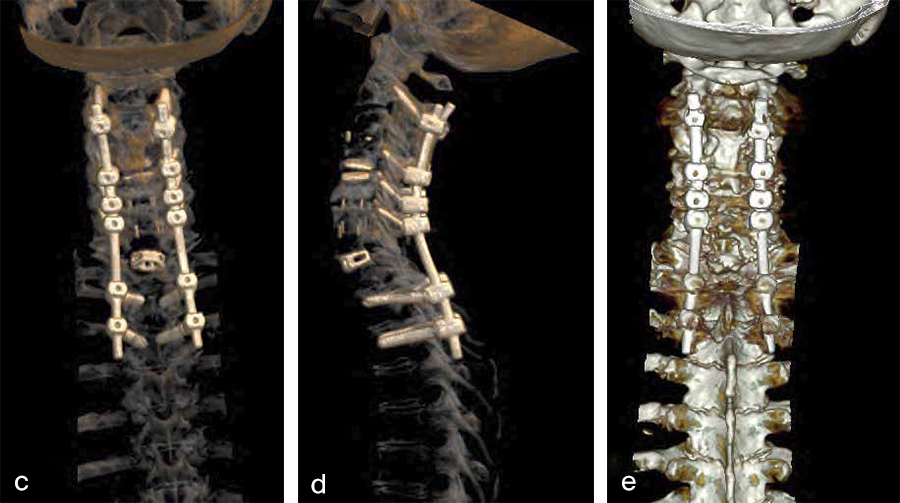

Second, a posterior revision surgery was performed including implant removal of the posterior instrumentation between C2 and C4 followed by a laminectomy of C7 with bilateral foraminotomy of the C8 nerve routes. Re-instrumentation with isthmic screws at the level C2, lateral mass screws at the level C4, C5, and C6, as well as bilateral pedicle screws at the level T2 and T3 was performed using the new Symphony system (DPS). The Symphony system offered the opportunity to place 4.0 mm screws in the previous loosened screw location at the level C2. The 3.5 mm screws were placed in C4, C5, and C6, and 5.5 and 5.0 mm screws at T2 and T3, respectively. The 4.0 mm rod allowed a good direct connection between the cervical spine isthmic and lateral mass screws and the thoracic pedicle screws, providing adequate stability and allowing excellent reduction. An intraoperative image is shown in Fig 5. Postoperative x-ray evaluations are displayed in Fig 6ae.

Postoperative imaging (Fig 6a-e), showing:

AC DF C7/Th1 (Syncage C) and posterior stabilization with Symphony of C2, C4, C5, C6, Th1, and Th2 using 3.5 (C4/5/6) 4.0 (C2), 5.0 (TH2) and 5.5 mm (Th1) screws and 4.0 rods.